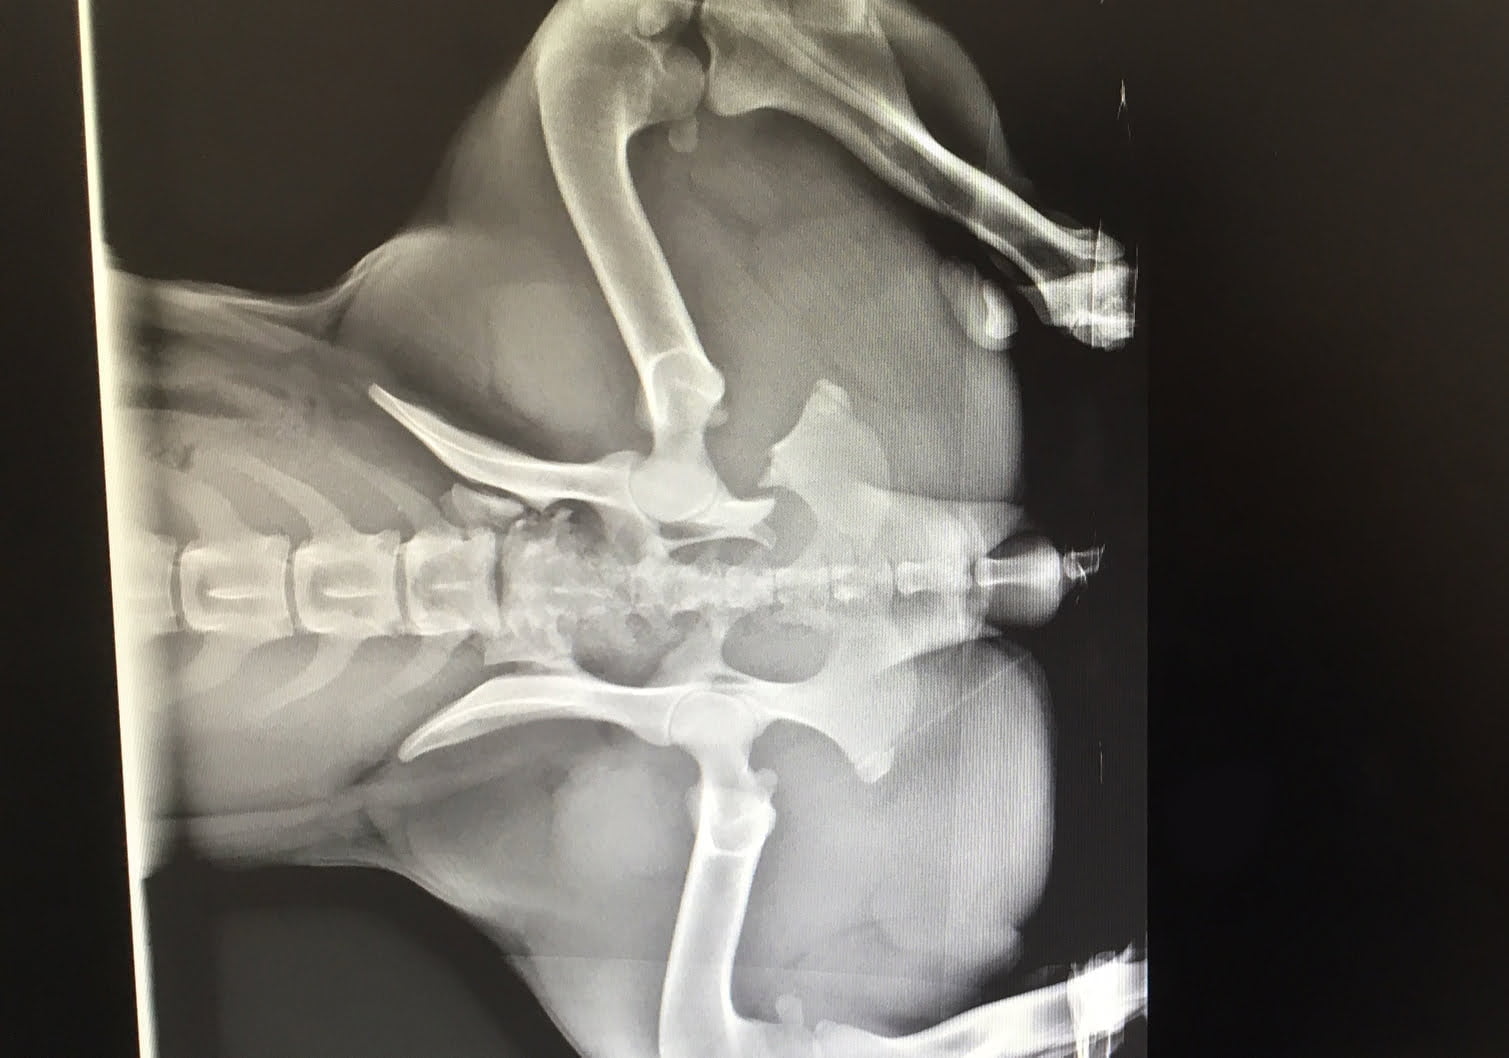

During her last visit, Mia and her foster family received excellent news: Mia’s pelvis was setting nicely. Mia is now being guided through daily physiotherapy exercises so that she can completely recover. She will soon be looking for a permanent home to call her own, where she can continue to receive proper follow-up care.

Thanks to the x-ray machine donated by a generous donor in memory of her cat Charlie, our veterinary team was able to quickly assess the extent of Mia’s injury and take regular follow-up X-rays to monitor her recovery. It is thanks to your donations that the Montreal SPCA can provide this kind of care to animals that have been in serious accidents. From the bottom of our hearts, we thank you for your generosity!